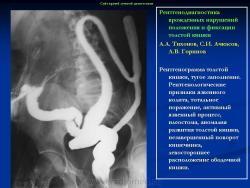

Варианты и аномалии развития толстой кишки.